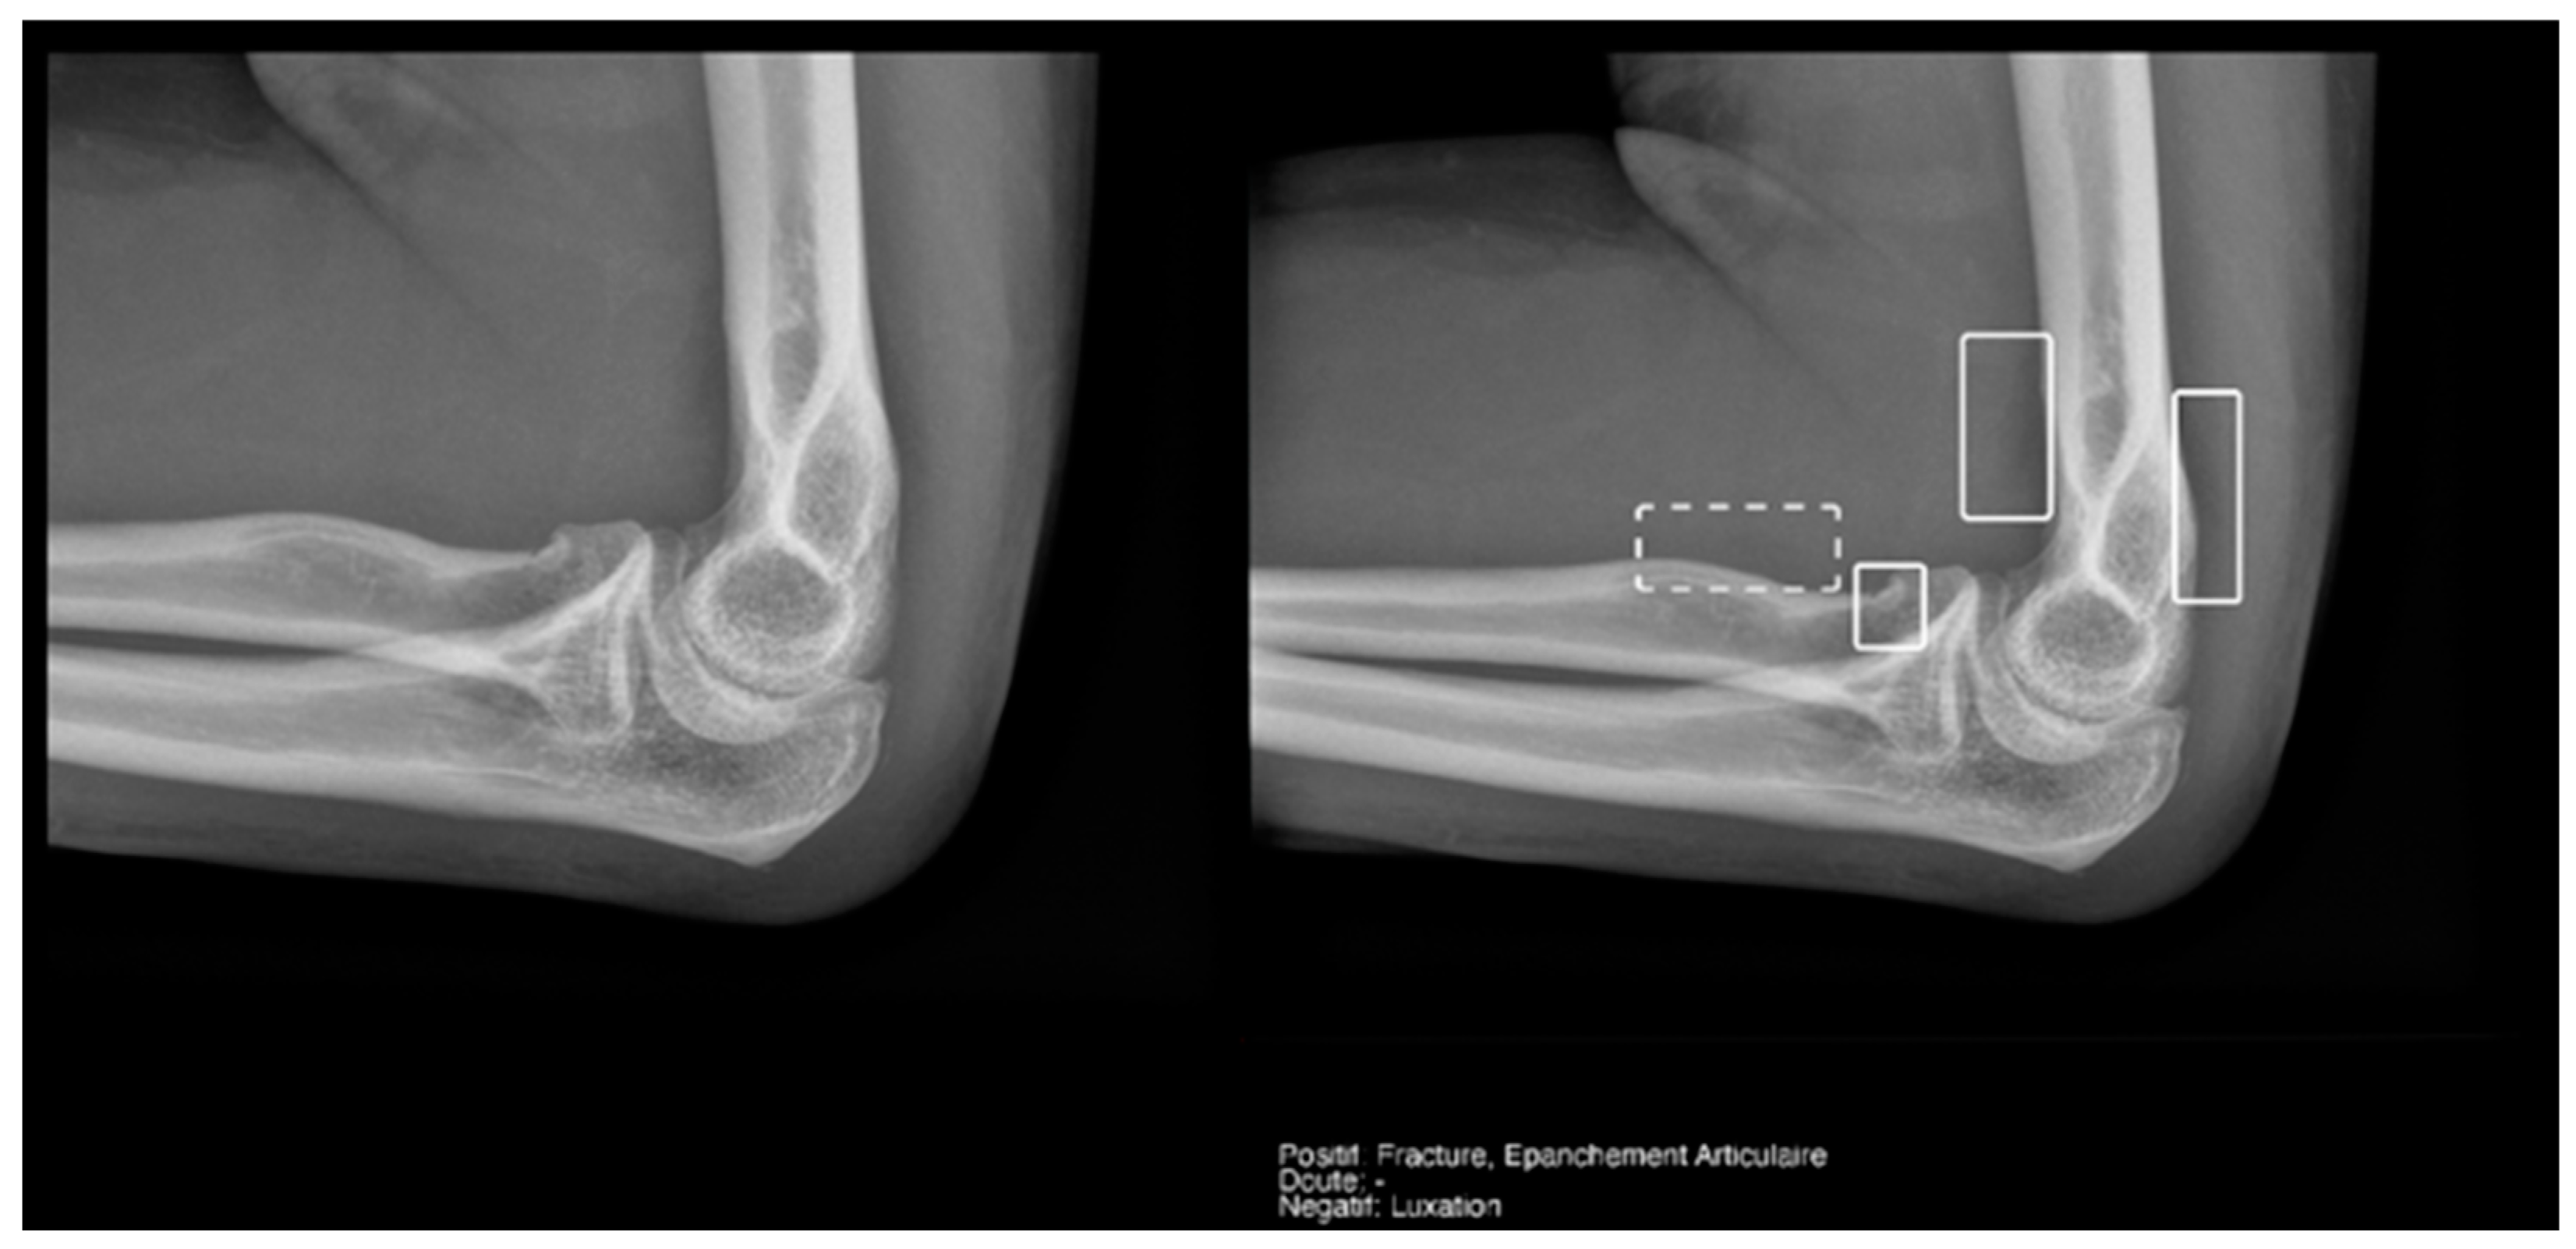

Regarding the detection of dislocations (Table 4), we observed better sensitivity results in the resident’s reading compared to that of the AI, with a high sensitivity of 77.8% in the overall cases, which improved to 84.6% in the large joint group. In contrast, the AI showed lower sensitivity values, with 35% in the overall cases and 35.7% in the large joints. However, specificity values were excellent for all readings and groups, reaching between 99.5% and 100%. (Figure 9 and Figure 10).

Figure 9.

Glenohumeral joint dislocation that was correctly recorded by both the AI and radiology resident.

Figure 10.

Pelvic fracture and coxofemoral dislocation, which was recorded as negative by AI but correctly detected by the radiology resident.

Regarding the detection of joint effusion in the elbow (Table 5), the low prevalence of joint effusion in our sample affected the calculation of the variables. Although a sensitivity of 100% was found in both the Milvue and the resident’s readings, the confidence intervals were very wide. On the other hand, specificity and negative predictive values were more reliable for both readings, with the AI reading standing out in particular, showing a specificity of 94.4% (Figure 12).

Figure 12.

Radial head fracture and joint effusion, correctly detected by AI and radiology resident.